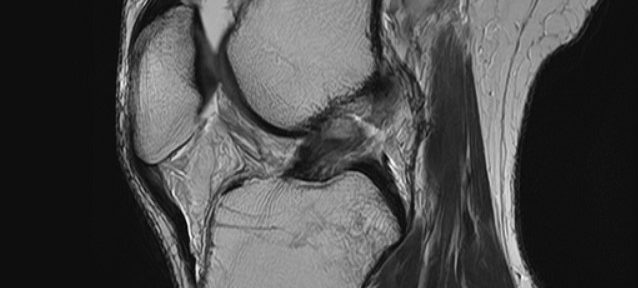

Case 42: A 42-Year-Old Singaporean Woman Who Healed a Complete ACL Tear with Evo-Devo Exercises Instead of Surgery

A 42-year-old woman from Singapore chose Evo-Devo Exerc…